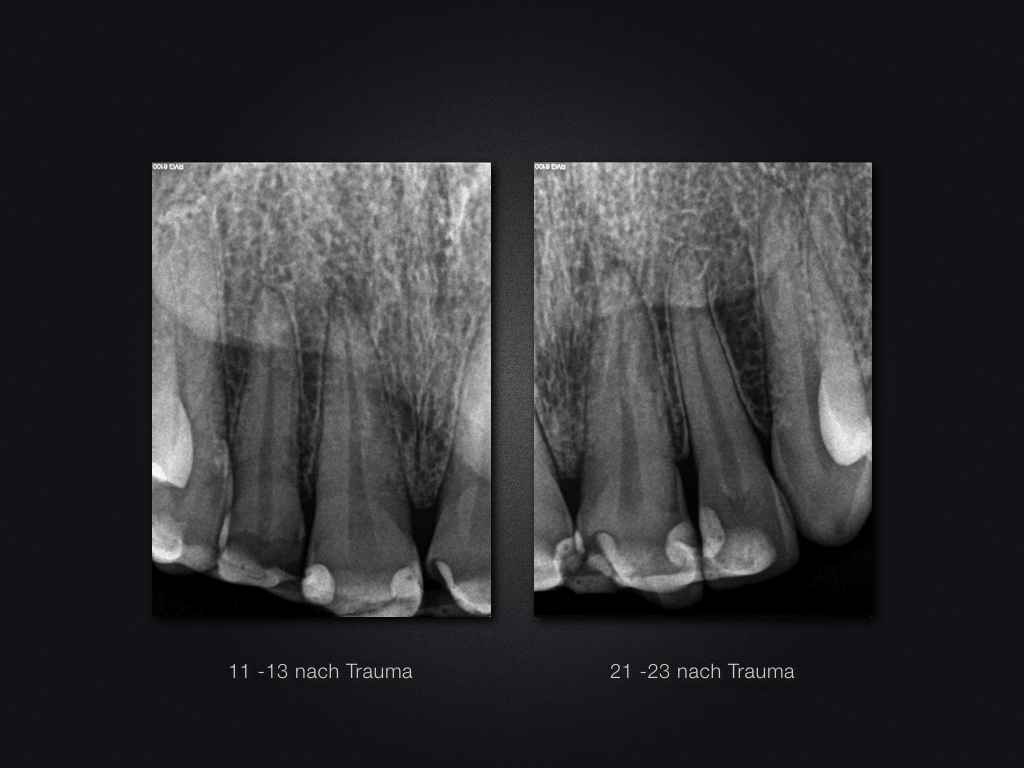

11 21 D.002

Trauma-„Zweitversorgung“